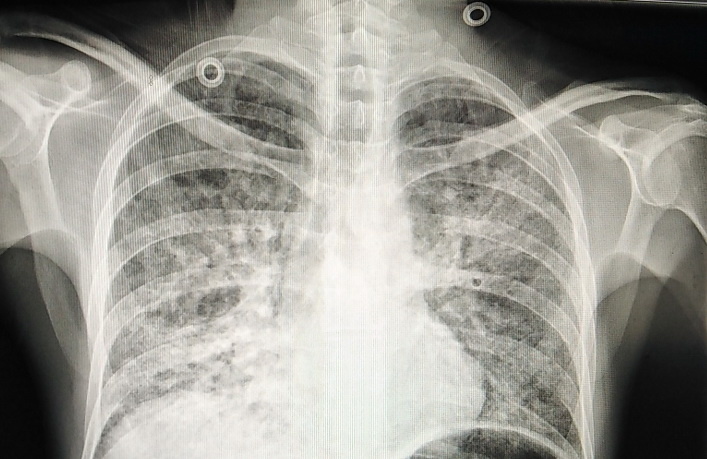

Двусторонняя полисегментарная пневмония. У людей в расцвете сил она встречается нечасто.

После выполнения рентгеновского снимка дежурный терапевт приёмного отделения пришёл ко мне, чтобы обсудить тактику. При таком тяжёлом поражении обоих лёгких сомнений нет – пациент заслуживает самого внимательного отношения, и лечить его надо в условиях реанимации. Откуда такие тяжёлые изменения у молодого пациента?